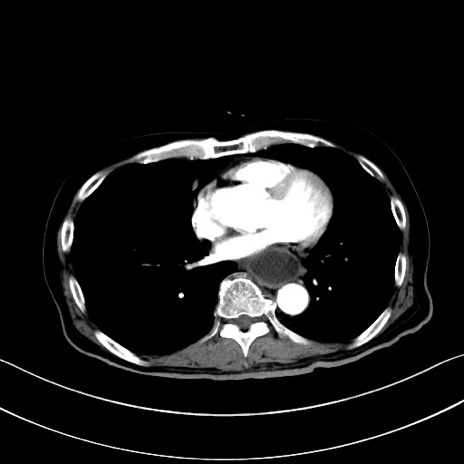

冠状断像

【症例】60歳代男性

【主訴】嘔吐

【現病歴】胃癌にて胃全摘後。食思不振が悪化し、夜中に嘔吐することがある。

【既往歴】胃癌、胃全摘、脾摘、胆摘後

【データ】WBC 5900、CRP 10.56